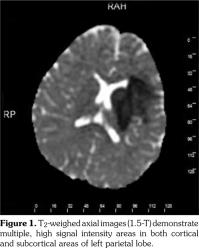

Based on these clinical findings, the patient was diagnosed as HSP, and the skin biopsy showed leukocytoclastic vasculitis with histopathologic evidence of immunoglobulin (Ig) A and M deposition based on direct immunofluorescence staining. A written informed consent was obtained from the parent of patient. The patient was being followed-up as an out-patient. On the 15th day of his follow-up, he admitted to the emergency department by sudden focal tonic- clonic convulsions and unconsciousness. He was not able to use his right hand and foot, also he could not talk. His blood pressure was 105/70 mmHg. Fundoscopic examination was unremarkable. The physical examination showed aphasia, right sided central facial paralysis, and hemiplegia on the right. Deep tendon reflexes were exaggerated and there was extensor plantar response on the right side. Cerebellar functions and sensory testing were normal. In acute laboratory evaluation, serum electrolytes and glucose levels were normal. Immediate 1.5 Tesla magnetic resonance imaging (Magnetom Avanto, Siemens Medical Solutions, Erlangen, Germany) demonstrated multiple, high signal intensity areas on T2-weighted images in both cortical and subcortical areas of the left parietal lobe (Figure 1). Magnetic resonance angiography revealed narrowing and irregularities in the lumen of left middle cerebral artery resembling vasculitis (Figure 2). Electroencephalography showed diffuse generalized delta slow waves of moderate amplitude without epileptiform discharges. Renal angiography and mesenteric vasculature were normal. The patient was diagnosed as cerebral vasculitis due to HSP. Intravenous pulse methylprednisolone (30 mg/kg/day) was given for three consecutive days; subsequently the patient received oral steroids (2 mg/kg/day) for cerebral vasculitis. Because of the unchanged clinical status of the patient, pulse cyclophosphamide therapy was begun. Patient received 500 mg/m(2)/day pulse cyclophosphamide monthly for three months. He showed clinical improvement after cyclophosphamide therapy. The follow-up magnetic resonance angiography, performed 15 days after the initial one, demonstrated substantial improvement of cerebral lesions (Figure 3). His steroid treatment was stopped by tapering within six months. He had speech therapy and also physical rehabilitation and therapy for two years. He has been followed-up without any sequel for four years.